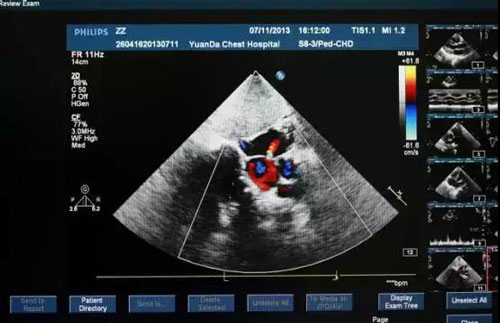

心臟檢查方式二:心臟彩超

“此項(xiàng)目能檢查房間有多大,墻結(jié)不結(jié)實(shí),漏不漏水。”

醫(yī)生通過在患者體表移動(dòng)探頭,能清楚地看到心臟結(jié)構(gòu),相當(dāng)于醫(yī)生的“透視眼”,如心壁厚薄、心腔大小、心臟瓣膜啟閉等情況,還能直觀顯示心肌的運(yùn)動(dòng)狀況及血流動(dòng)力情況,提示心肌缺血的部位等,且對(duì)人體沒有任何損傷。